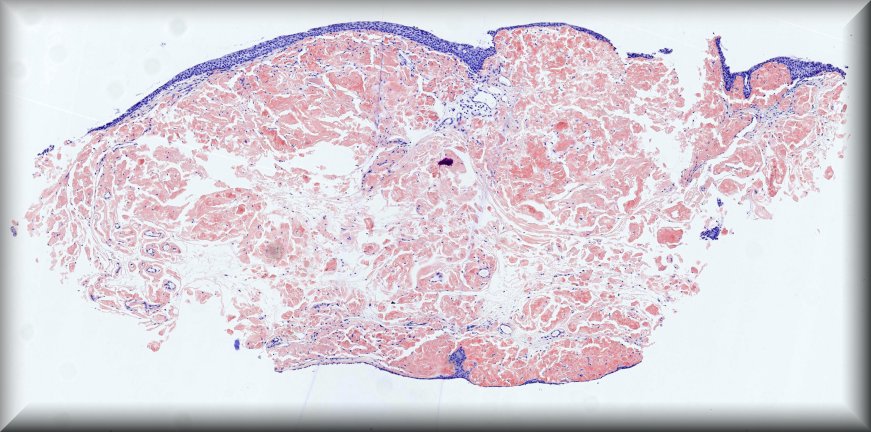

Jolique van Ipenburg (Nijmegen): 50-year-old male, retinoblastoma survivor, with conjunctival squamous lesion. Protocol |